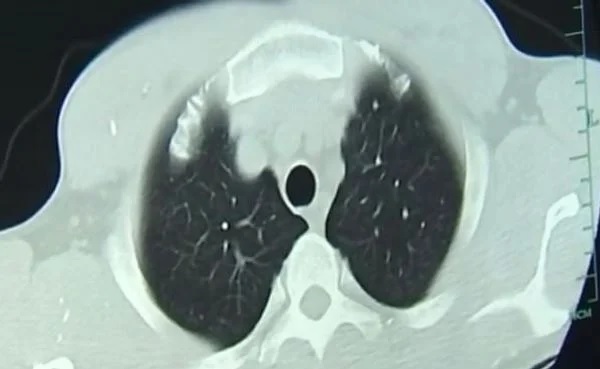

In spite of just a month passing since he consumed the half-cooked pork, specialists immediately recognized the reason for Zhongfa’s seizures and swooning episodes. His body was totally contaminated with tapeworms. These unwanted visitors had made themselves at home in his mind, lungs, and different pieces of his body. The worm hatchlings had spread all through his body by means of his circulation system.

The hatchlings entered Zhongfa’s body through his stomach related framework and went through his circulation system to his cerebrum and lungs. These child worms wriggled into his body tissue and shaped pimples. On the off chance that these pimples rot, they can cause diseases. Individuals with this equivalent issue as Zhongfa frequently report cerebral pains, seizures, visual deficiency, and dementia. Notwithstanding, these side effects don’t necessarily in every case show up right away. Once in a while it can require a long time for the worm hatchlings to arrive at the cerebrum and lungs.

When these hatchlings structure pimples close to the mind or sensory system, it can bring about a perilous contamination called cysticercosis. On account of Zhongfa, the hatchlings had caused various space-possessing sores in his cerebrum, as well as pimples in his lungs and chest muscles.

Dr. Huang Jianrong from the Partnered Clinic of Zhenjiang College Institute of Medication was worried about Zhongfa’s condition. That is the reason he requested mind and chest X-rays for the patient.

“He had various sores in his cerebrum, yet he likewise had blisters in his lungs and chest muscles,” Dr. Huang said. “Various patients answer contrastingly to the contamination, contingent upon where the parasites are. For this situation, he encountered seizures and blacked out, however others with sores in their lungs could encounter a ton of hacking.”